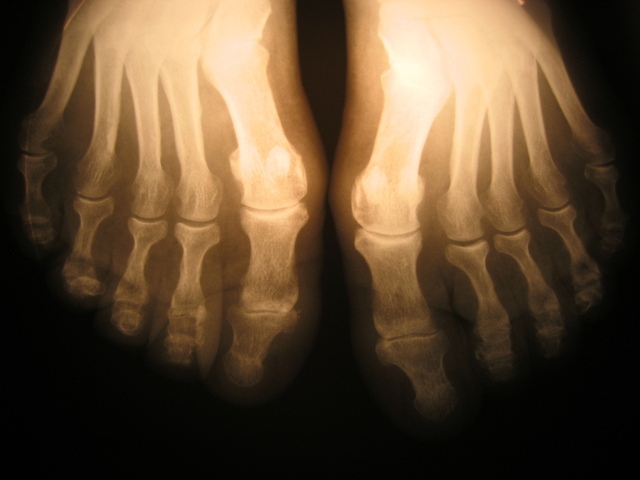

However recently I experienced what it’s like to feel helpless, vulnerable and reliant on others. After what shall forever be known as ‘the dumbbell incident’ which resulted in a broken metatarsal, I got to experience these things first hand.